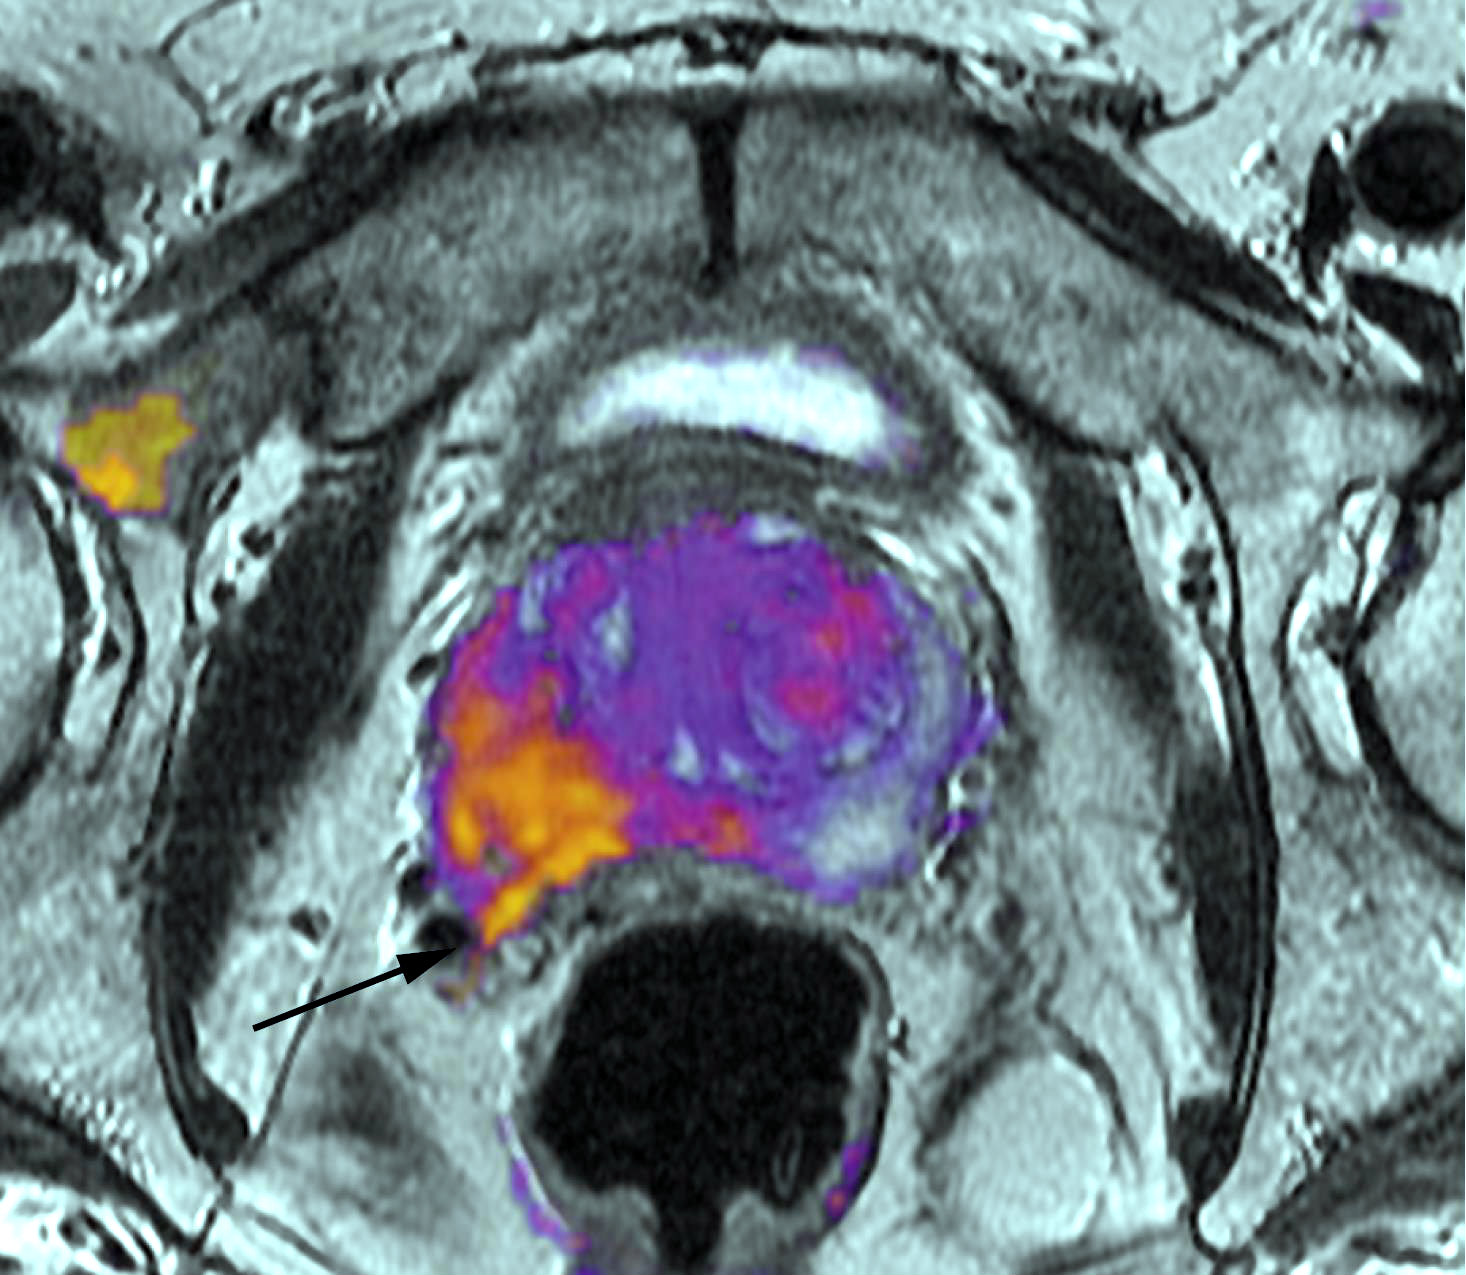

Diagnóstico y tratamiento del cáncer de próstata. Una revisión

JAMA, 28 de junio de 2017 Los avances en el diagnóstico y tratamiento del cáncer de próstata han mejorado la capacidad de estratificar a los pacientes por riesgo y han permitido a los médicos recomendar la terapia basada en el pronóstico del cáncer y la preferencia del paciente. El tratamiento inicial con quimioterapia puede mejorar la supervivencia en comparación con la terapia de privación de andrógenos